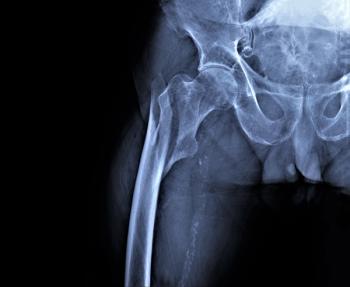

Data from a new study is sounding the alarm on trends in the trajectory of hip fracture incidence among the general population.

A new study examined how adolescent physical activity can impact hip strength and potentially reduce the risk of osteoporosis later in life.

Physical training can preserve and even significantly bolster the bone mass of the hip and femoral neck in individuals under caloric restriction, according to a systematic review and meta-analysis of 13 randomized clinical trials.